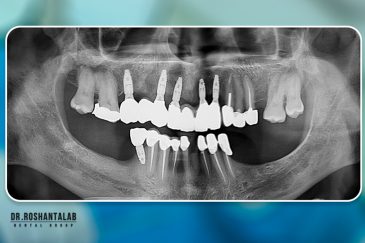

کلینیک تخصصی دکتر حسن روشن طلب با همکاری جمعی از متخصص ایمپلنت دندان و جراح فک و صورت بنام در حال فعالیت می باشد. این مجموعه مأموریت خود را ارائه خدمات تکمیلی دندانپزشکی در زمینه درمان های تخصصی و عمومی به شرح ذیل انجام می شود.

بهره مندی از دانش علمی و تجربه بالای موسس و جراحان این کلینیک، همچنین امکانات و تجهیزات به روز و کارآمد از جمله ویژگی های منحصر به فرد این کلینیک است. همچنین با ارائه خدمات درمانی با کیفیت و هزینه مناسب دندانپزشکی در رشت، تهران، اصفهان و استانبول ترکیه توانسته است در این سال ها لبخند رضایت بر صورت مراجعه کنندگان عزیزمان بگذارد.

انتخاب بهترین متخصص ایمپلنت که به تکنیکهای روز دنیا مسلط باشد، تضمینکننده سلامت فک و زیبایی لبخند شماست. در کلینیک دندانپزشکی دکتر روشنطلب، ما با بهرهگیری از تجهیزات دیجیتال در ۵ شعبه فعال (تهران، اصفهان، رشت و استانبول ترکیه)، خدمات تخصصی کاشت ایمپلنت دندان را برای بیمارانی که کیفیت و دقت برایشان اولویت دارد، ارائه میدهیم. در این متد، پروسه درمان با ظرافت بالا انجام شده؛ راهکاری ایدهآل برای کسانی که به دنبال درمان بدون درد با بالاترین نرخ موفقیت هستند.